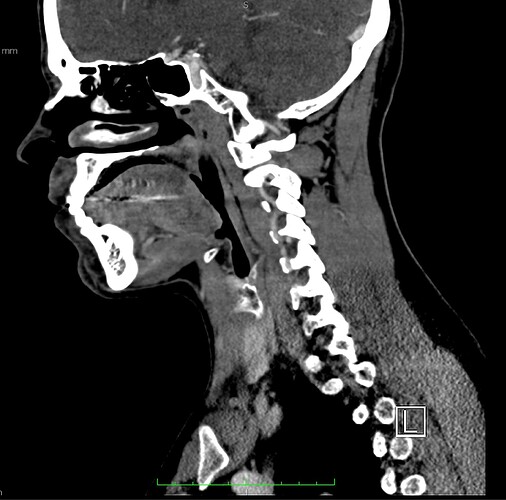

So, 2 years ago was the first time I came across Living with Eagle, filled with descriptions of all my symptoms, and a slew of scans showing very obvious bone chunks in the neck. Since I studied bio in college, and these bones are obvious, I figured I’d take a stab at looking at my own past scans and, low and behold, mild–but present–ossification of my stylohyoid ligament. Perhaps more relevant in my case, in the process of learning enough of the anatomy to understand axial images I noticed another weird thing–my right external carotid artery is in the wrong place. Instead of sitting lateral to my hyoid greater cornu, it’s medial. Hmm.

Tonsil surgery did solve the problem of my tonsils hurting, because they were gone, but no resolution of other symptoms. This was a year ago. I’ve been to PT, SLP, and now back to PT while I trial gabapentin for the neurologist. PT#2 discovered a bunch of significant atrophy in my upper right shoulder/back, and, you guessed it it’s all right sided. I’ve since then, thanks to radiopedia and Netter’s, also explored my images and noticed a few other anomalies in my scans, including an extended right thyroid superior cornu which appears to be pressing strongly into my neck also in the general area of pain, and an occipital artery branching off and wrapping around the internal carotid. Frustratingly these also weren’t mentioned on rads reports. My swallow study by the SLP showed obvious asymmetry with my swallow, but the SLP reported it symmetric and radiology apparently doesnt read the A/P view in their modified barium swallow studies? This is not inspiring faith in the academic institution I attended, but what can I possibly know they dont?